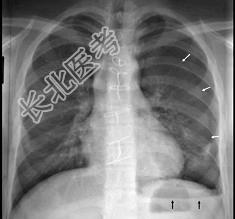

- 单项选择题18岁,男, 被人殴打后胸痛,请结合胸片选出最可能的诊断 ( )

A、血气胸

B、气胸

C、胸腔积液

D、肺气肿

E、肺挫伤